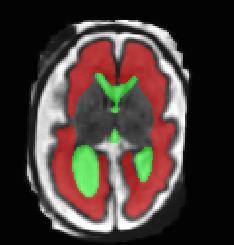

Limiting failures of machine learning systems is of paramount importance for safety-critical applications. In order to improve the robustness of machine learning systems, Distributionally Robust Optimization (DRO) has been proposed as a generalization of Empirical Risk Minimization (ERM). However, its use in deep learning has been severely restricted due to the relative inefficiency of the optimizers available for DRO in comparison to the wide-spread variants of Stochastic Gradient Descent (SGD) optimizers for ERM. We propose SGD with hardness weighted sampling, a principled and efficient optimization method for DRO in machine learning that is particularly suited in the context of deep learning. Similar to a hard example mining strategy in practice, the proposed algorithm is straightforward to implement and computationally as efficient as SGD-based optimizers used for deep learning, requiring minimal overhead computation. In contrast to typical ad hoc hard mining approaches, we prove the convergence of our DRO algorithm for over-parameterized deep learning networks with ReLU activation and a finite number of layers and parameters. Our experiments on fetal brain 3D MRI segmentation and brain tumor segmentation in MRI demonstrate the feasibility and the usefulness of our approach. Using our hardness weighted sampling for training a state-of-the-art deep learning pipeline leads to improved robustness to anatomical variabilities in automatic fetal brain 3D MRI segmentation using deep learning and to improved robustness to the image protocol variations in brain tumor segmentation. Our code is available at https://github.com/LucasFidon/HardnessWeightedSampler.